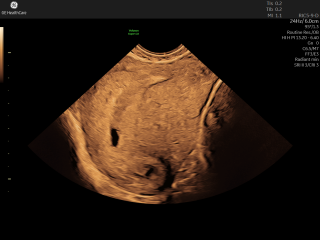

Sonnyelodie88 · 27/02/2026 11:50

Have had an early scan, first midwife said twins, second said only a bleed is possible - confused - see scan photo. thoughts anyone??

How far along were you when you had the scan. Its definitely too early to really have an opinion. If they are sacs there is nothing in them at this stage that I can see and the bottom dark spot could be part of a bleed. The only way your going to know is to go back for a scan a little later on, say closer to 8 weeks gestation.

ToKittyornottoKitty · 28/02/2026 14:21

It looks like it’s just too early to say. How far along do you think you are?